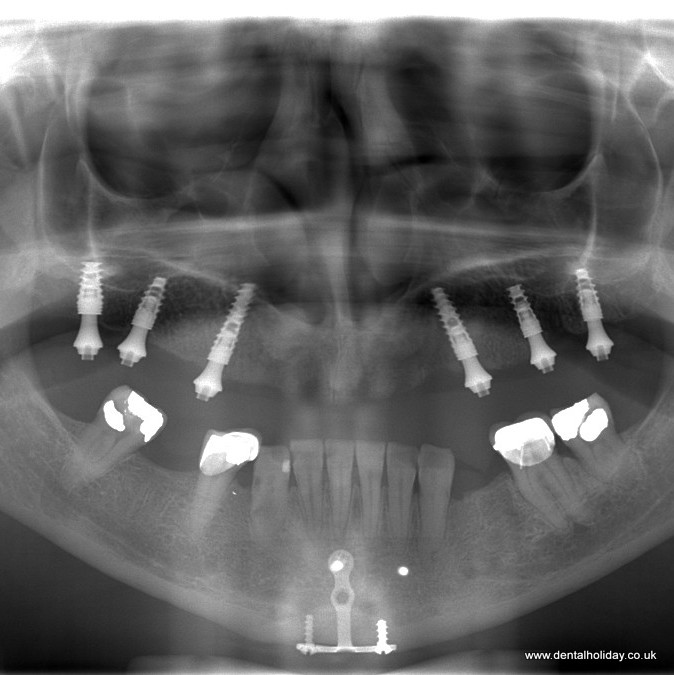

She came over with her daughter to visit us for a dramatic change. As you can see from her X-ray, there are no teeth in the upper jaw, and we placed 6 dental implants witch eventually supported 12 new teeth.